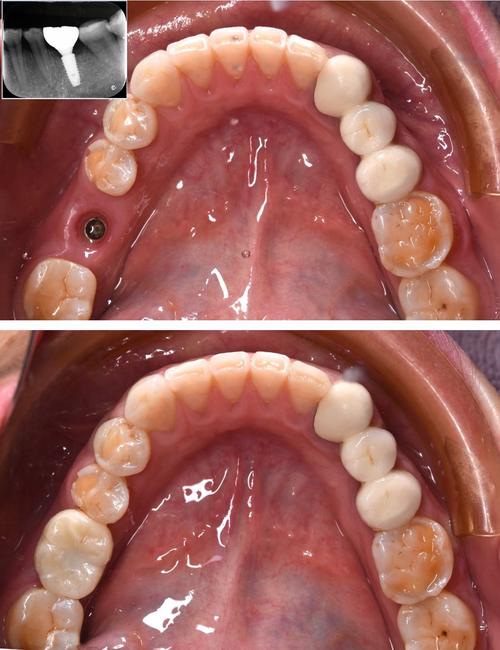

- 种植检查:通过CBCT评估牙槽骨骨量、密度、神经血管位置,确定种植体直径、长度及植入位点。

种植体植入(正畸中期,1-2小时)

当缺牙间隙、骨条件满足后,在局部麻醉下植入种植体:

- 时机选择:通常在正畸排齐后、关闭间隙前进行,此时牙齿移动已趋于稳定,种植体植入后不易受正畸力量干扰;

- 植入位置:需与正医生沟通,确保种植体位于理想位置(如牙长轴方向、与邻牙距离≥1.5mm),避免正畸移动后种植体与邻牙接触或咬合干扰。

种植体植入后需等待3-6个月骨结合,期间继续完成剩余正畸治疗(如关闭间隙、调整咬合):

- 骨结合期间,正畸力量需轻柔(避免使用强支抗),定期复查种植体稳定性;

- 骨结合完成后,取模制作种植基台与牙冠,同时完成正畸保持器制作,确保治疗效果长期稳定。